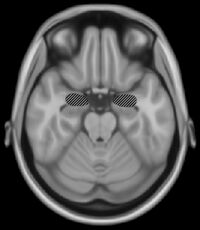

Amygdala

The amygdala.

Located above the hippocampus in the medial temporal lobes are two amygdalae (singular "amygdala"). The amygdalae are associated with both emotional learning and memory, as it responds strongly to emotional stimuli, especially fear. These neurons assist in encoding emotional memories and enhancing them. This process results in emotional events being more deeply and accurately encoded into memory. Lesions to the amygdalae in monkeys have been shown to impair motivation, as well as the processing of emotions.[5]